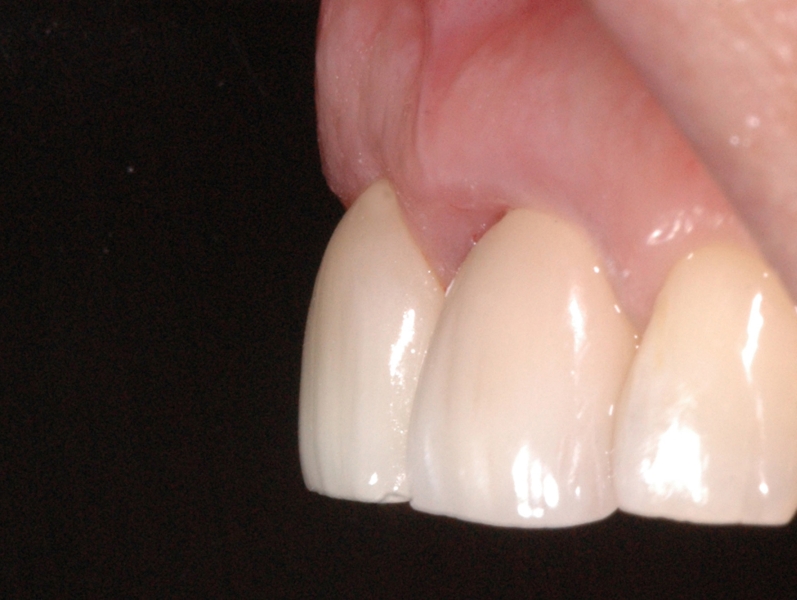

16/18 - Final restoration 15 months after implantation and stability of root coverage in regio 23GBR together with soft tissue augmentation with mucoderm® and maxresorb® - Dr. S. Scherg

17/18 - Final restoration 15 months after implantationGBR together with soft tissue augmentation with mucoderm® and maxresorb® - Dr. S. Scherg